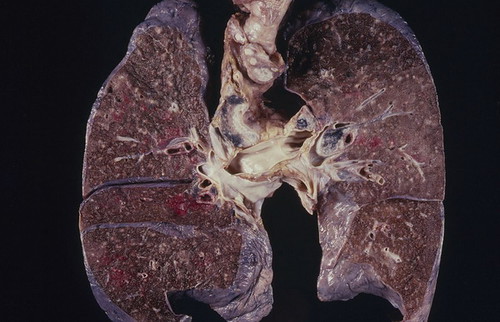

At Easiofy, three women engineers built ImagiXAI to speed cancer planning and bring advanced imaging to remote India.